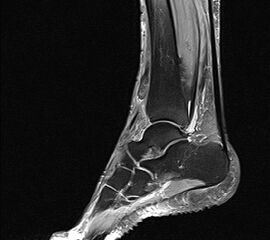

Selektive Kraftprüfung des MTA: Durch die Fixierung der Zehen in Hyperextension werden die Zehenstrecker funktionell ausgeschaltet. Damit kann die Kraft des MTA selektiv getestet werden.

Abbildung 1

Bei substantieller Schädigung der M. tibialis anterior Sehne bzw. seiner Innervation (N. peroneus) sind klinische Befunde wie Ausfall bzw. Reduktion der Dorsalextension und reduzierte Supination und Adduktionskraft zu erwarten. Bei aktiver Dorsalextension lässt sich eine Eversion des Rückfußes und die Hyperextension der Zehen beobachten 89. Die selektive Testung des MTA kann unter funktioneller Ausschaltung der Zehenextensoren stattfinden. Hierzu ist die Stabilisierung der Zehen in maximaler Dorsalextension notwendig (Abbildung 1).